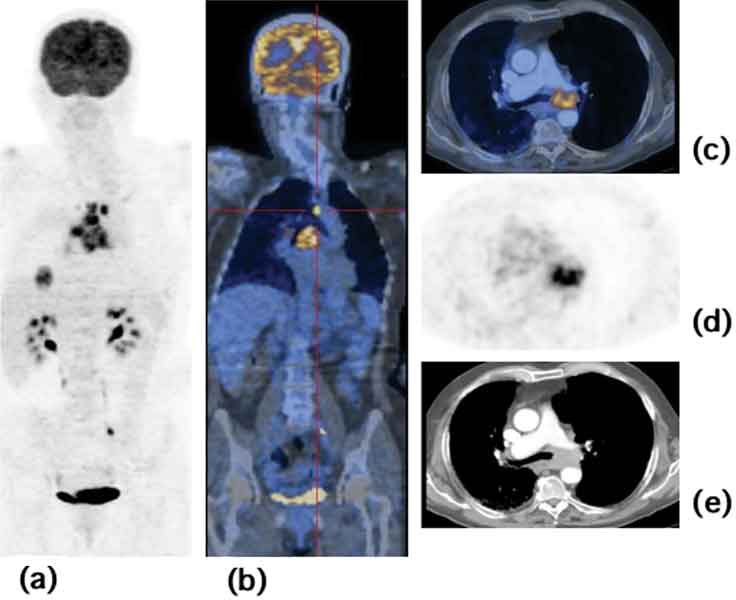

Per un paziente con insufficienza cardiaca, verificare se il cuore potrebbe beneficiare di interventi di bypass o di uno stent è fondamentale per garantirsi la sopravvivenza. Una tecnica di imaging, la tomografia a emissione di positroni (PET) con il fluorodeossiglucosio agente di imaging (FDG), i medici possono ottenere le informazioni di cui hanno bisogno per prendere decisioni più accurate per stabilire il trattamento, secondo la ricerca pubblicata nel numero di aprile di The Journal of Nuclear Medicine (JNM).“L’esame PET è talmente accurato che in base ai risultati ottenuti si puo’ decidere il percorso di cura da intraprendere, con scarse possibilità di errore. Beneficio per paziente e sistema sanitario.”ha detto Kevin C. Allman, MD, specialista senior , PET e reparto di medicina nucleare, del Royal Prince Alfred Hospital nel New South Wales, Australia, e co-autore dell’articolo sul JNM.

Secondo lo studio rioportato sul JNM I vantaggi di utilizzare FDG PET per valutare l’attività e l’efficienza del miocardio – per vedere se il tessuto cardiaco trae beneficio dallla rivascolarizzazione, o il ripristino del flusso sanguigno al cuore, al fine di ripristinare la ridotta capacità di pompaggio – sono stati a lungo osservati.

Le malattie cardiovascolari rimangono la prima causa di morte negli Stati Uniti. Gli interventi per riparare i danni e ripristinare il flusso sanguigno al cuore può aiutare alcuni pazienti con insufficienza cardiaca congestizia, prima che sia troppo tardi. Anche se altre tecniche di imaging semplicemente danno il tessuto del cuore come morto (leso, cicatriziale) o sano (efficiente), l’imaging molecolare conferisce ai medici un quadro più completo di come il cuore lavori, compreso il tasso di flusso di sangue e il metabolismo del cuore. La riduzione del flusso sanguigno potrebbe essere un segno di arterie bloccate; mantenuto il metabolismo, il tessuto cardiaco in questa regione è ancora vitale, e sarebbe opportuno ripristinare il flusso normale. Con queste informazioni, i medici dovrebbero essere in grado di pianificare meglio i trattamenti – cardiopatie e pazienti dovrebbero avere migliori risultati.